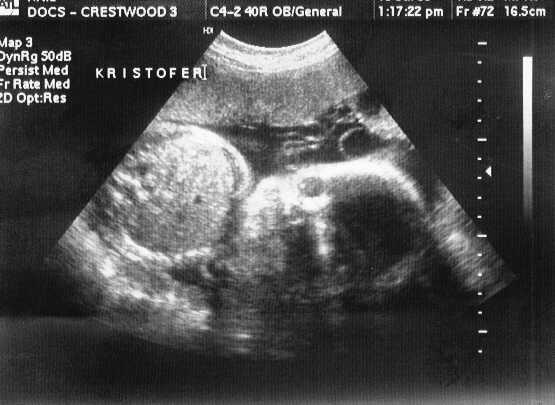

This is KRISTOFOR HENRY (or Kristofer). I was only kidding about RICO!

sono-0719-k1.JPG - 25.1 K